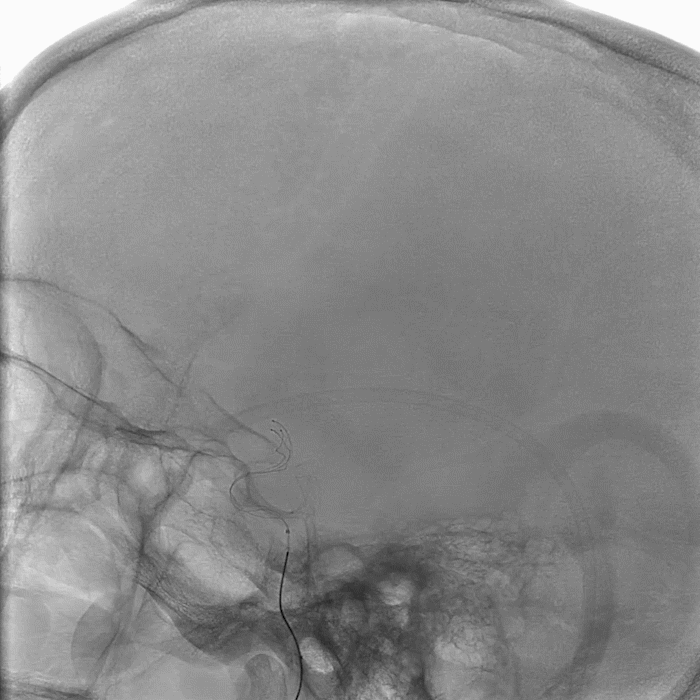

在泥鳅导丝、V18支撑导丝导引下,8F导引导管直接进入左颈内动脉C1近段,取5F的Navien中间导管,置于颈内动脉岩骨段,取可操纵微导丝在微导管辅助下小心通过血栓闭塞段到大脑中动脉M1,微导管通过闭塞段后回撤至颈内动脉末端,手推造影剂提示左侧大脑中动脉可见前向血流通过闭塞段,首过阳性,考虑左侧大脑中动脉慢性狭窄基础上急性闭塞,予替罗非班0.75mg静脉符合,并0.3mg/h持续静脉泵入维持;微导管在微导丝辅助下送大脑中动脉M1段以远,退出微导丝,将(4.0*25 NeuroHawk®取栓支架)在透视下放入左侧大脑中动脉M1段并释放支架取栓,支架打开欠满意,约5分钟后予撤出支架及微导管,此过程中50ml注射器保持负压抽吸血液,取出一个血栓,大小约0.2cm×0.5cm。

微导管到位

支架到位

复查造影提示左侧大脑中动脉再通,残余重度狭窄,远端血流可,未见血栓异位栓塞,mTICI分级3级(穿刺至再通时间1.07h)。行DynaCT见左侧额叶、顶叶皮质少许高密度灶,观察18分钟复查造影提示血管狭窄无回缩,结束手术,未中和肝素,保留右股动脉鞘,局部无菌纱布予覆盖并加压包扎。术后患者镇静状态,双侧瞳孔等大,疼痛刺激左侧肢体无活动。患者左侧大脑中动脉经支架取栓完全再通。

术后侧位